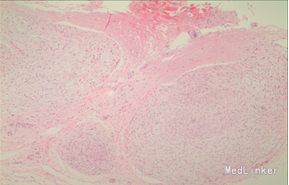

诊断 处理

完善相关检查,在气管插管麻下行“左额眶部占位病变切除术”。术后病理诊断为“(左眼眶)丛状神经纤维瘤”。术后给予患儿脱水、营养脑神经、抗感染等对症治疗。复查CT未见明显异常。

患儿术后2周左眼睑下垂较术前好转。双侧瞳孔反射、眼球活动均无异常。 丛状神经纤维瘤主要发生于眼睑,在出生后或幼年时期即出现症状和体征。侵袭范围广泛,包括眼睑、眶内软组织、眶骨和邻近的脑、颞部等。眼部最早和最多见为上、下睑软性肥厚,皮下瘤组织增生,使上、下睑隆起。眼睑皮肤常有淡棕色色素斑,眼球向前突出和向下移位。眼球突出虽然很显著,但向眶内纳入并不困难。肿瘤组织可直接侵袭眶内各种结构,上睑提肌首先被波及,引起上睑下垂,上举不足或不能。MRI可准确显示病变的范围尤其显示病变与邻近结构的关系,也可清楚显示其他部位伴发的肿瘤,但难以清晰显示眶壁骨质改变。手术治疗是必要的,手术切除应注意以下问题:1.眼睑病变的切除;2.眶内病变的处理;3.提上睑肌的处理;4.眶骨缺失的处理。丛状型术前诊断容易,但治疗较为棘手,易复发。